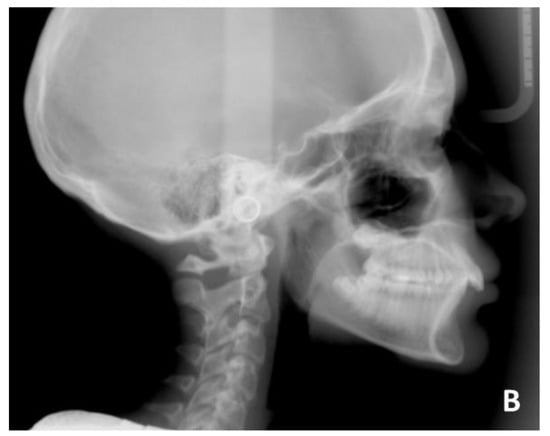

The treatment was conducted exclusively with clear aligners and followed the protocol for the resolution of the deep bite that was described above. It lasted approximately 18 months, with only one little refinement. At the end of the treatment, the resolution of the deep bite and an important leveling of the patient’s curve of Spee was clearly evident, as can be seen in the comparison between the initial and final orthopantomography.

The exposure of the lower incisors at the end of the treatment was normal, the upper and lower crowding was resolved, and the dental class was corrected. In fact, at the end of the treatment, the patient was in molar and canine class I. Cephalometric analysis (Table 2) showed skeletal deep bite, skeletal class II, and better inclination of upper and lower incisors. At the end of the treatment, intra- and extra-oral photos of the patient and X-rays were taken (Figure 12 and Figure 13) and, after few days, a removable Essix for long-term retention was delivered. Final cephalometric tracing is showed in Figure 14.

Figure 13. Post-treatment radiographic of case number 1: (A) orthopantomography; (B) lateral cephalogram.